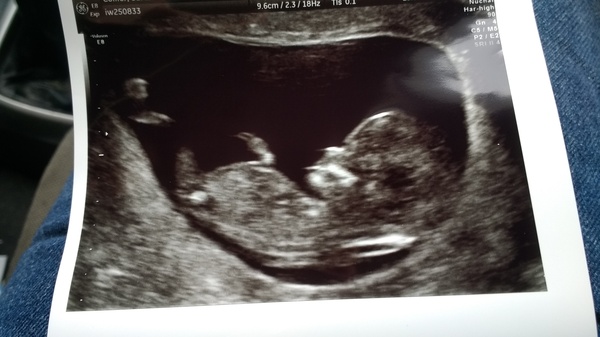

Nub theory!?

Those nub experts.. what does this look like to you!?!

Gir💝

Luna I think girl. Witsender I think maybe a boy x